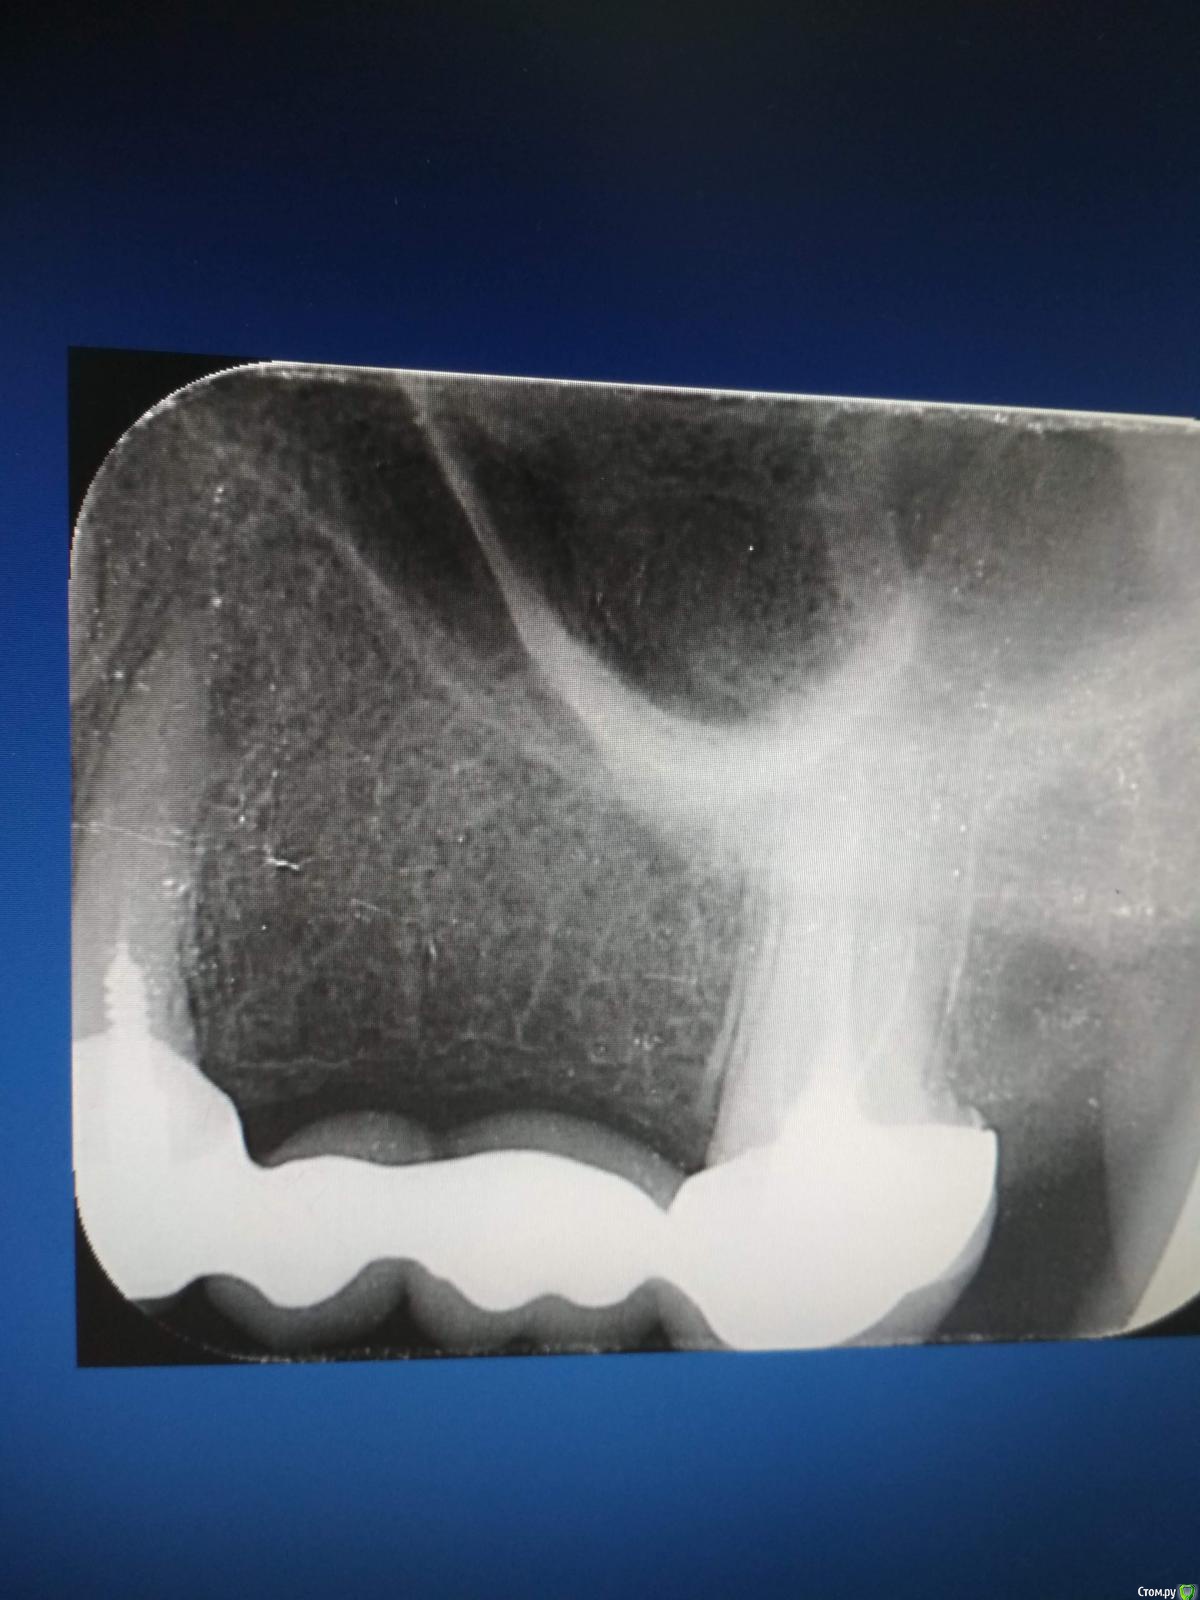

Arsinoya Опубликовано 5 октября, 2019 Автор Поделиться Опубликовано 5 октября, 2019 Вот еще такой Ссылка на комментарий

Мартовский Опубликовано 7 октября, 2019 Поделиться Опубликовано 7 октября, 2019 Шестых зубов у вас нет, ни с лева ни с права, ни с верху ни с низу. Перфорация есть в левой четверке. Что делать, вам уже сказали: обратиться к другому врачу, по интернету такое не вылечить. Ссылка на комментарий